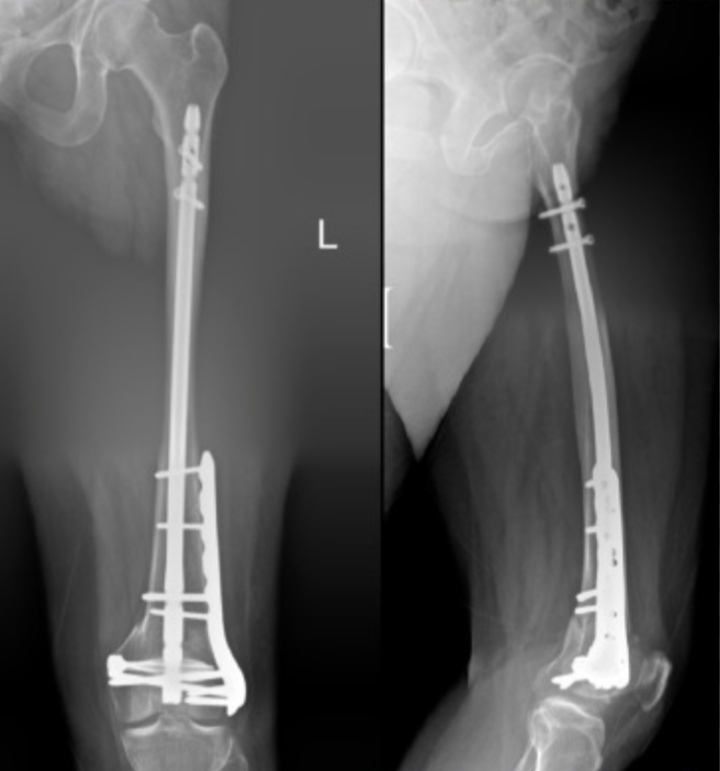

A fracture of the femur, or thigh bone, is a serious injury because it is the main weight-bearing bone in the body. Treatment usually requires surgery, and the two most common fixation options are intramedullary rods (nails) and plates with screws. Both are used to stabilize the bone and allow it to heal, but they differ in technique and application.

This method involves inserting a metal rod into the hollow center of the femur and securing it with screws at both ends.

Rods are commonly used for fractures in the middle section of the femur because they align well with the bone’s natural structure.

This technique involves fixing a metal plate along the outside of the femur using screws placed above and below the fracture.

Plates are often chosen for fractures at the ends of the bone or when detailed reconstruction is required.

Rods are placed inside the bone, while plates are fixed externally. Rods generally allow earlier weight-bearing and are less invasive, whereas plates provide more precise control in complex or joint-related fractures.